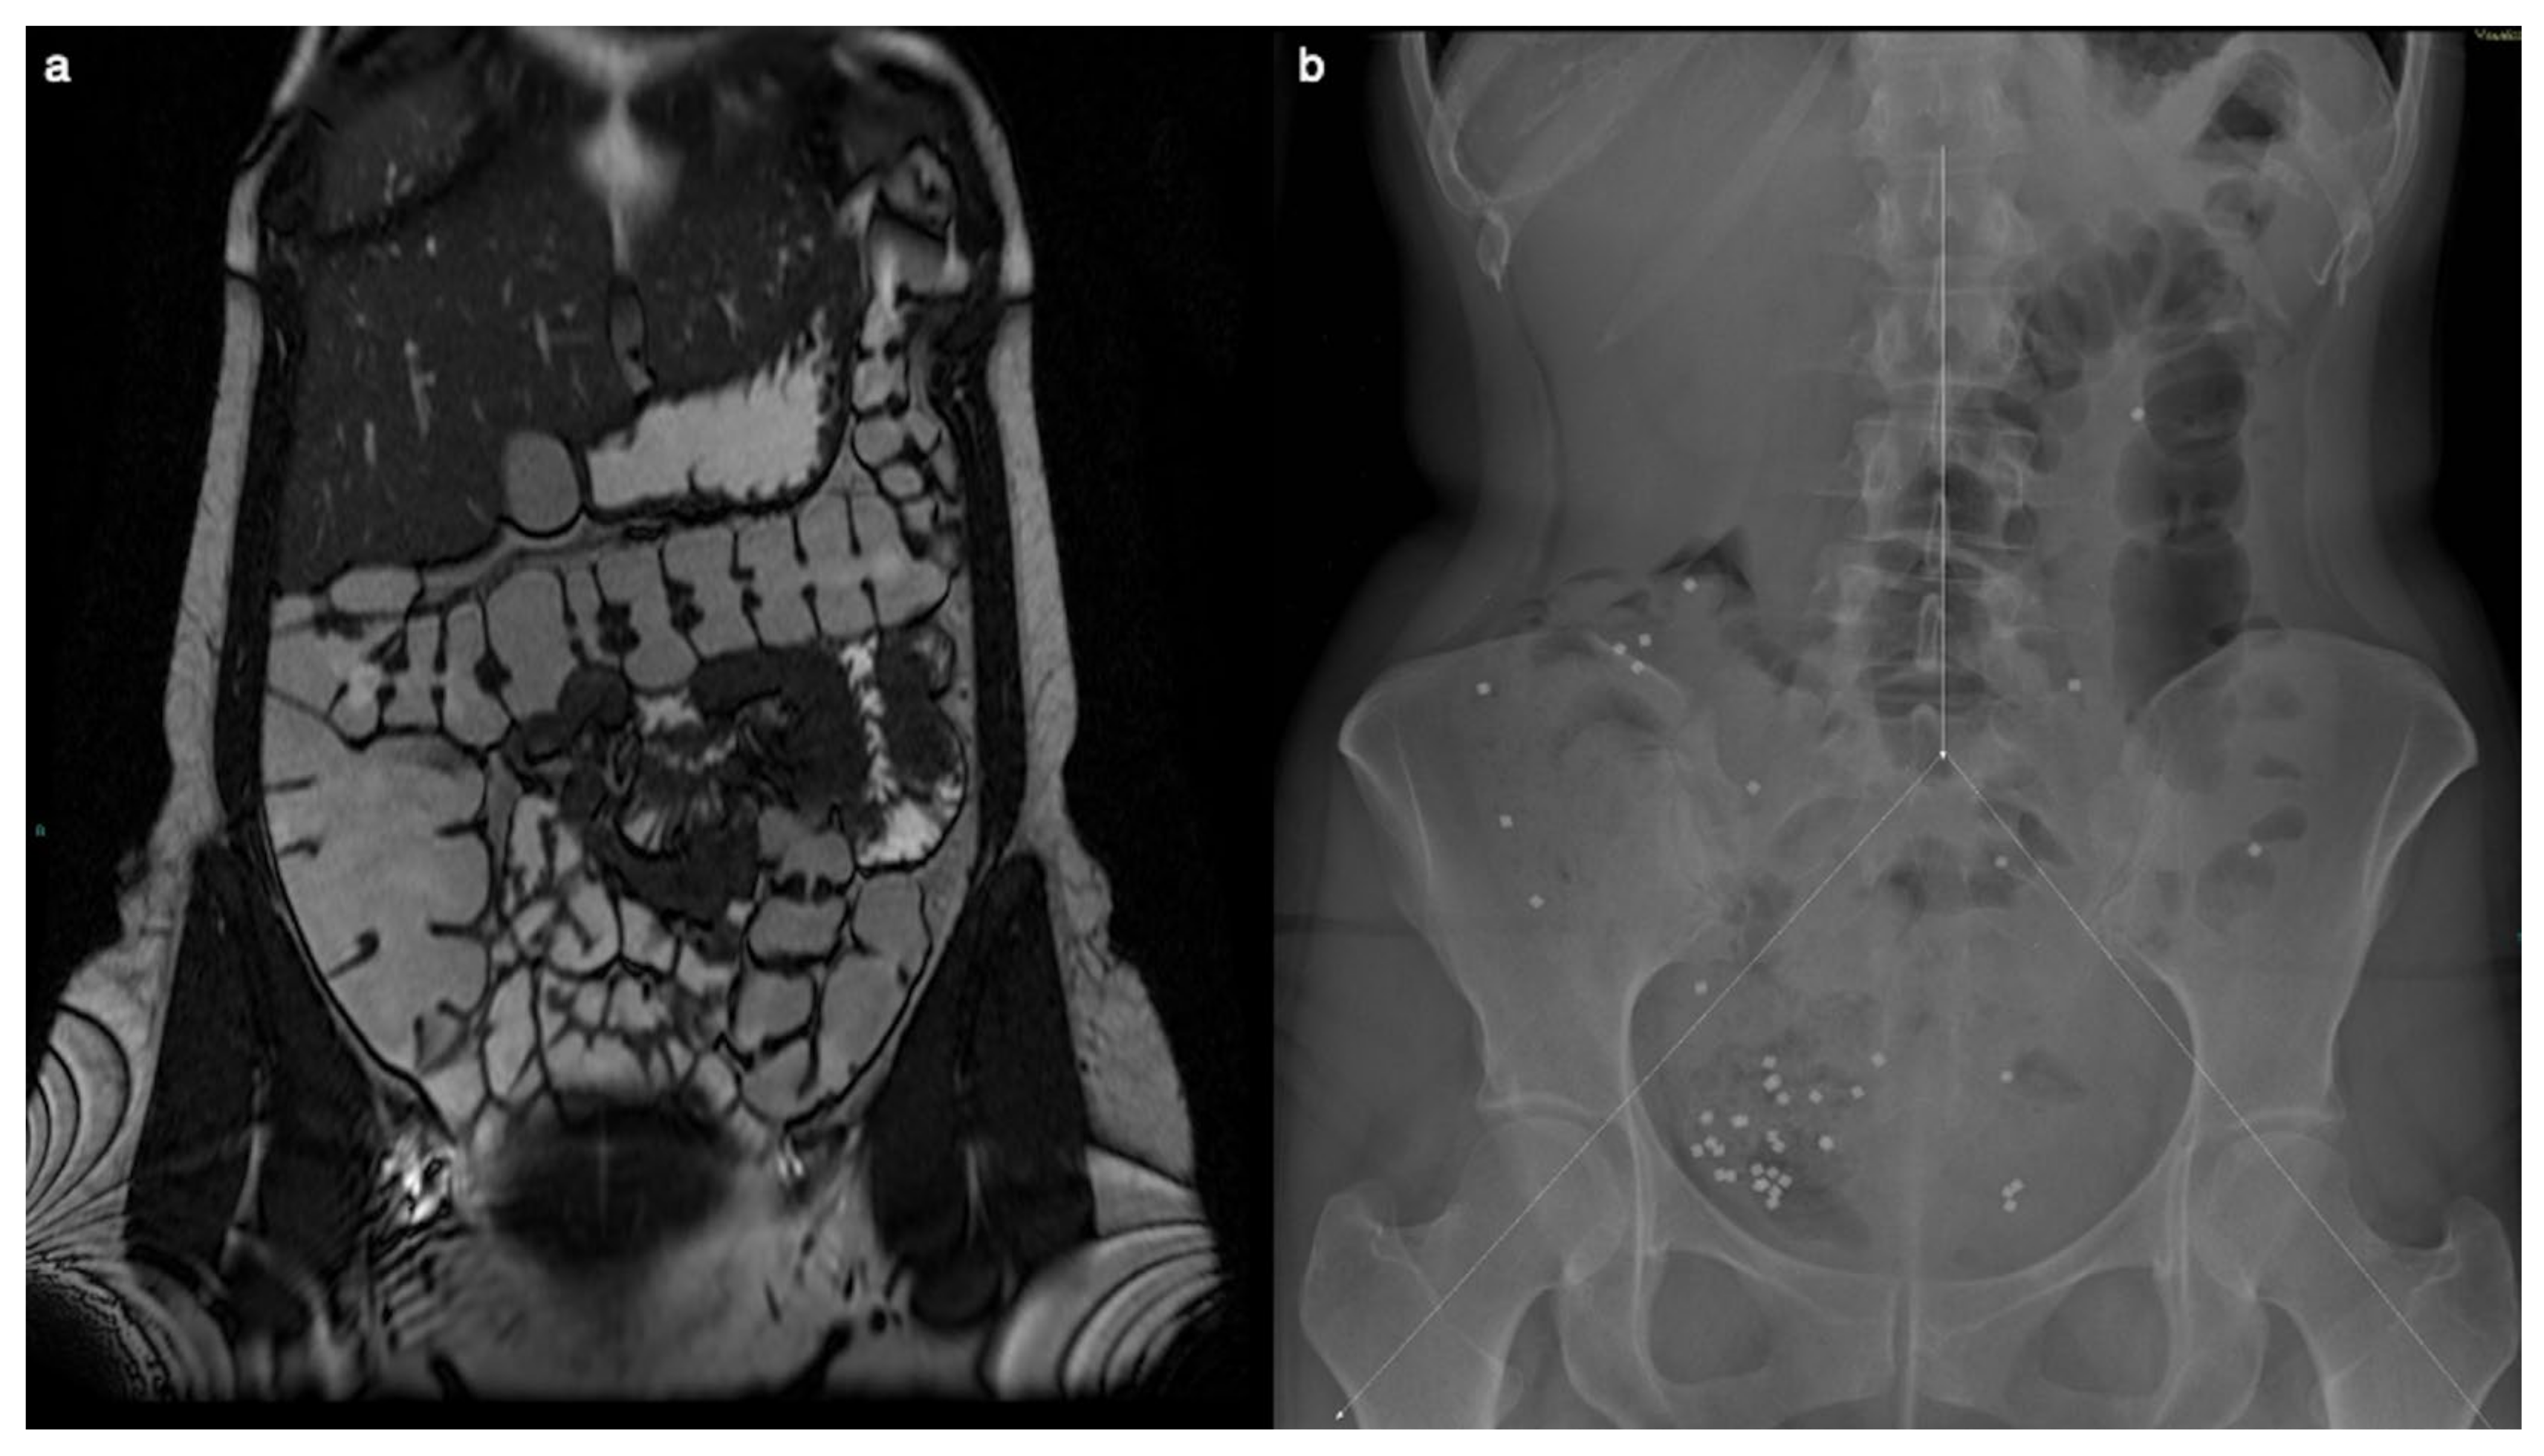

Transit time and gastrointestinal motility exams were performed. The examination indicated a delayed colonic transit time, with only 39 of 60 markers progressing within the anticipated timeframe. Furthermore, the distribution pattern of these markers pinpointed areas of diminished motility, with the majority of those accumulating in the right region of the colon. This concentration suggested a potential impairment in the normal functioning of the cecum and ascending colon. Such detailed observations from the X-ray findings enhanced the understanding of gastrointestinal motility disorders and guided subsequent diagnostic and therapeutic decisions (Figure 1).

MR enterography showed no significant alteration two years before surgery, when the patient was already symptomatic. The Coronal T2-weighted image does not show signs of right colon amyloidosis (a). The plain abdominal X-ray is divided into three segments, and radiopaque markers are counted for each segment (b). Measurement of colonic transit time based on radio-opaque markers shows delayed colonic transit time (39/60 markers). The distribution of the markers, with a majority in the right region (31/39), suggests reduced motility at the level of the cecum and ascending colon.